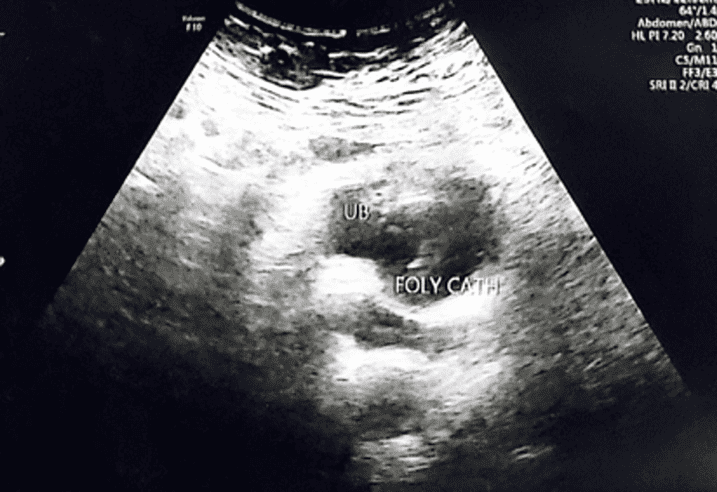

In addition, an abdominal ultrasound done to rule out to any urinary tract obstruction which was normal as shown in Figure 3-5. She was seen by the urology team and advised to keep the urinary catheter until her symptoms improve if not then to keep the Foleys until delivery. The patient was managed conservatively by serial bimanual examinations and an ultrasound was done on a weekly basis until patient condition spontaneously resolved at 13+2 weeks of gestation as shown in Figure 6.

Figure 5: Normal urinary bladder with Foleys catheter balloon showing